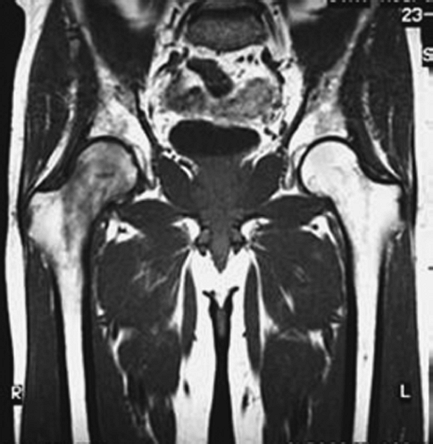

in diagnosing ON and should be obtained in all suspected cases in which

the plain radiographs are normal. In such cases, examination of both

hips should be performed because more than half of all cases are

bilateral. The changes noted on T1-weighted images typically include

subchondral signal changes located in the anterior superior quadrant of

the femoral head with a single-density line demarcating the

normal-ischemic bone interface (Fig. 4-1B). The

T2-weighted images may demonstrate a high-signal line inside a

low-signal region (double-line sign). As lesion size has been

associated with prognosis and response to therapy, MRI can be used to

determine lesion size or volume. 17